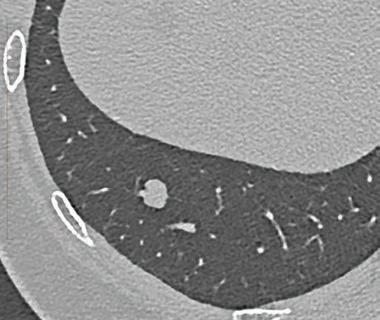

“In the future, every CT will be a photon-counting CT”

Prof. Gabriel Krestin

Erasmus Medical Center Rotterdam, Netherlands

“This will redefine our clinical decision-making right from scan one.”

Prof. Dr. med. Thomas Kröncke University Hospital Augsburg, Germany

“PCD-CT is so exciting because it provides information that existing CT detectors – the types that we’ve used for over 50 years – previously just couldn’t capture.”

Dr. Cynthia McCollough Mayo Clinic CT Clinical Innovation Center. USA

In March 2024 ChestRad introduced Photon Counting CT to Western Australia. But best not to listen to us. Find out what the experts have to say.

At Perth Radiological Clinic your chest imaging investigations are reported locally by WA’s largest team of fellowship trained accredited respiratory radiologists:

• Teaching hospital consultant radiologist appointments. Involved in multidisciplinary team meetings at FSH, MIHC, Mount Hospital, SCGH and JHC.

• RANZCR registered experts in occupational dust lung disease (RANZCR EODLD register).

• Expertise in all types of chest disease including malignancy, ILD, occupational lung diseases, lung cancer, vascular diseases and trauma.

PRC Specialist Chest Radiologist, Dr Stephen Melsom saysIf diagnosed early, particularly before symptoms develop, the progression of chest disease can be slowed

Dr Priority Line 9599 3929 perthradclinic.com.au